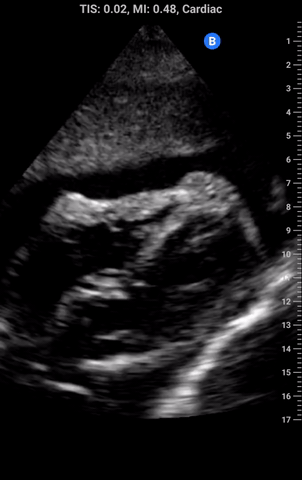

Effusion size: A small effusion can cause tamponade and a large effusion may not. More important than the size is the rate of accumulation. The pericardial sac has the ability to accommodate several litres of fluid, which if built up slowly even VERY large effusions will not cause tamponade. Therefore if you are concerned about tamponade and there is an effusion on ultrasound, your next move needs to be calling for help; using traditional physical examination assessing for significant pulsus paradoxus with a manual BP cuff is helpful to communicate urgency. There are many echocardiographic signs that can also suggest tamponade but outside of highly advanced users these are usually in the realm of cardiology as opposed to POCUS and remember tamponade is CLINICAL DIAGNOSIS. For example, the image on the right shows a moderate effusion but this patient had a pulsus of 18 with a resp rate of 40. They underwent pericardiocentesis and improved with drainage of just 20 ccs!